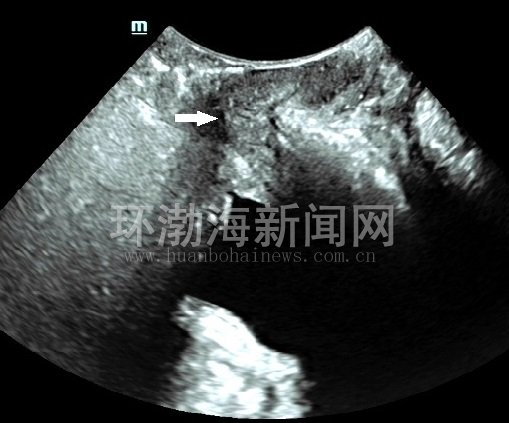

患者,张女士,30岁,阴道分娩1次,产后7个月,因咳嗽、大笑、打喷嚏时漏尿,产后便秘等症状到该院就诊。经该院盆底超声检查发现,在完成最大乏式动作(Valsalva)时膀胱内口呈锥形扩张,直肠前壁向后膨出;肛门内外括约肌完整,静息状态时肛提肌裂孔的三维图像呈规则的菱形,前、中及后三腔室结构完整紧凑,最大乏式动作时肛提肌裂孔面积稍有增大,但结构仍然完整紧凑。这样,一下子找到了过去不算病的“病根”,到相关科室对症治疗及解决了多日的“尴尬”。

图2:直肠前壁膨出